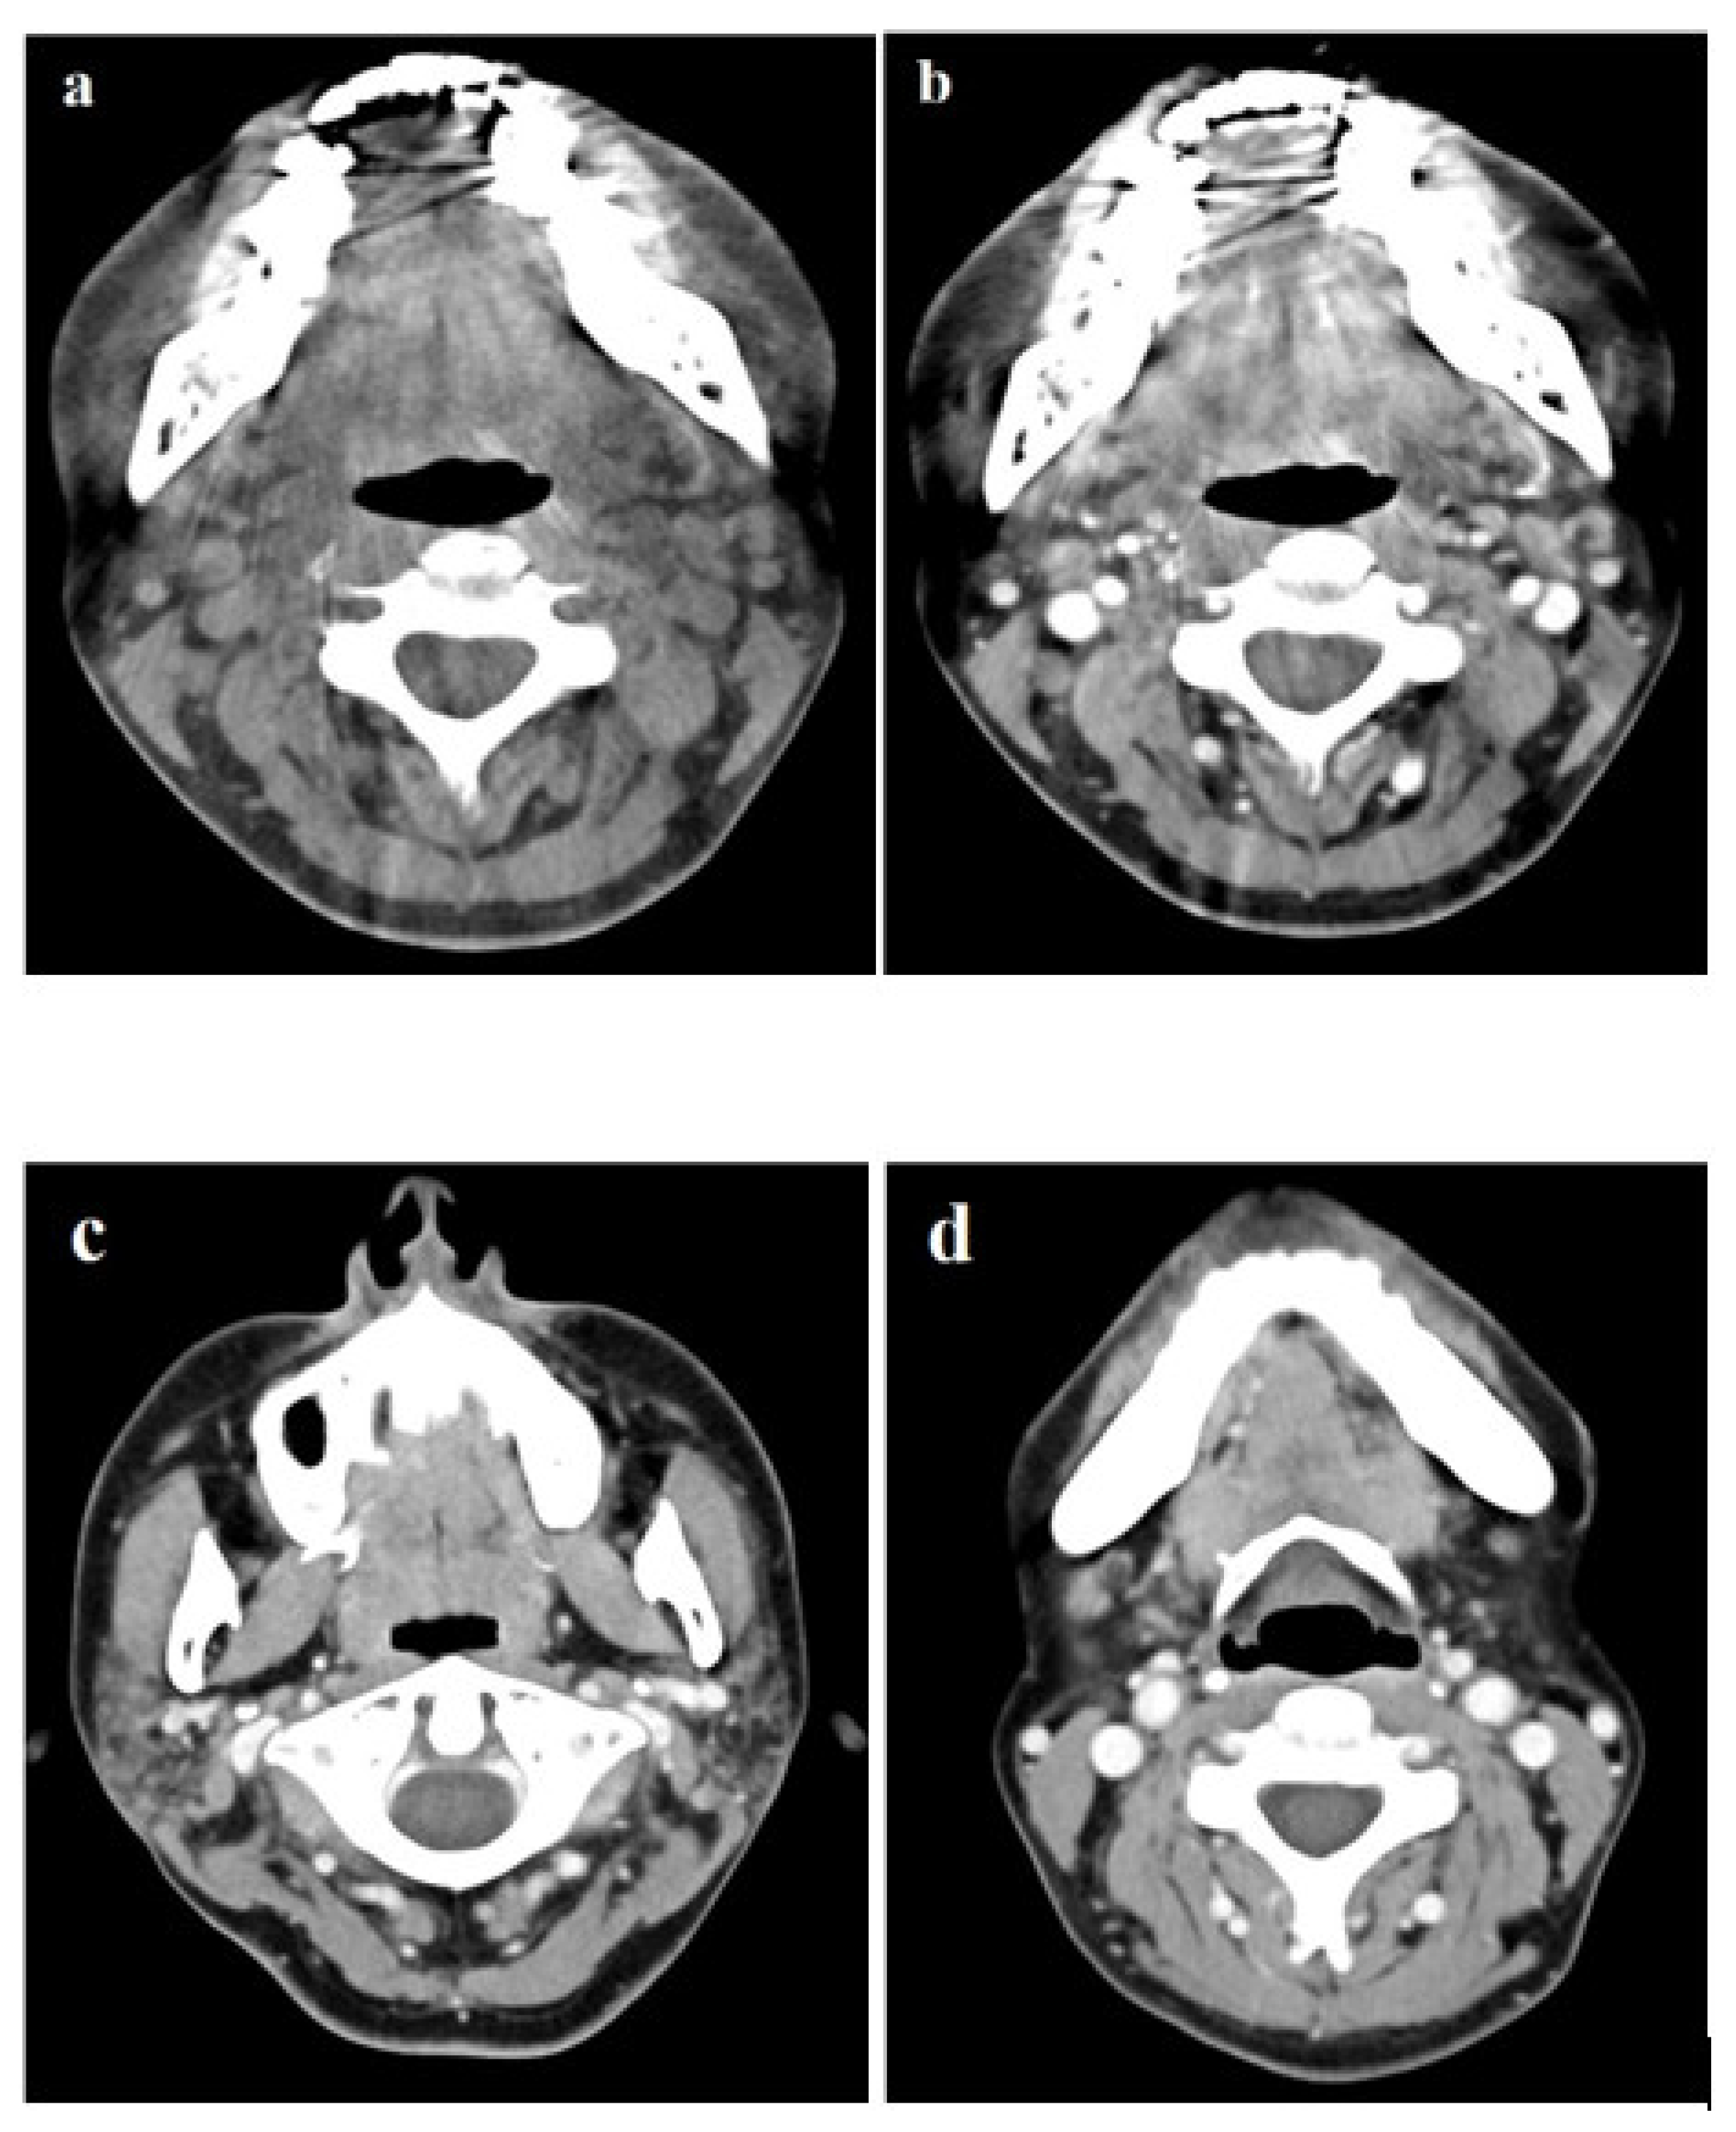

2. Case Report